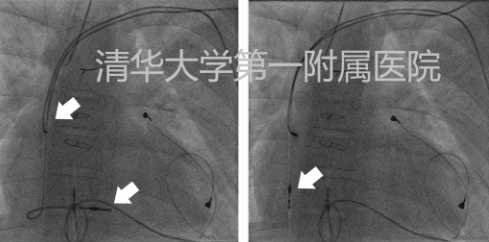

左图显示其心房及心室心内膜电极固定部位;右图为拔出心室电极过程